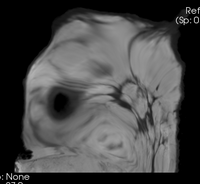

Bspline1 deformation only Deformation of Post image from unmasked BSpline 7x7x5 max 10mm

Bspline1 deformation only Deformation of Post image from masked BSpline 7x7x5 max 10mm